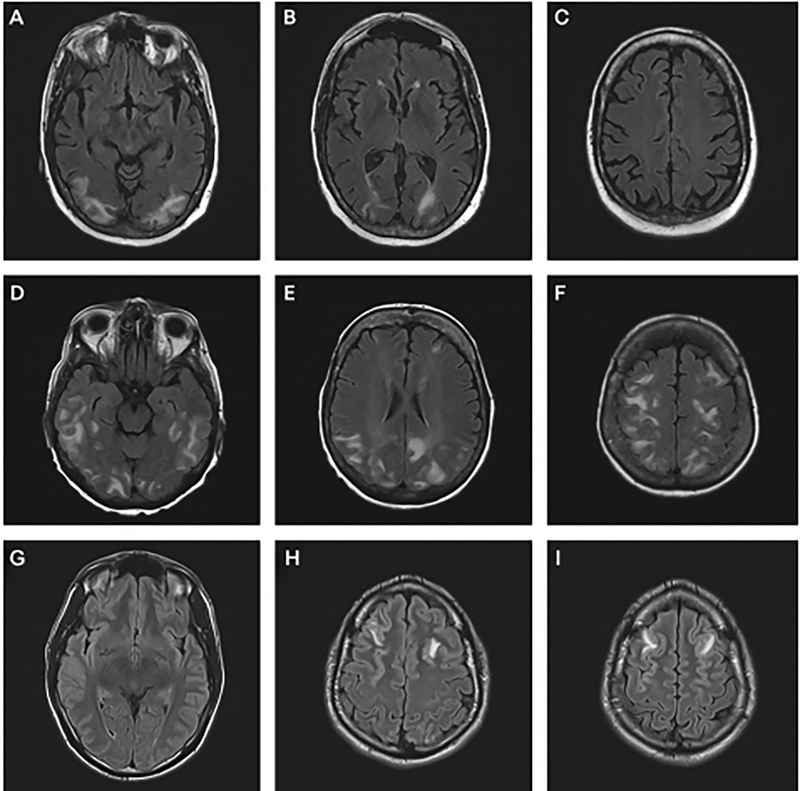

Chụp CT scan sọ não để đánh giá dịch não tủy

Nếu bệnh nhân có các dấu hiệu của tăng áp lực nội sọ, các biện pháp can thiệp ngay lập tức sẽ được thực hiện bao gồm bảo vệ đường thở, thông khí duy trì đủ oxy và cung cấp hỗ trợ tuần hoàn khi cần. Các biện pháp can thiệp để hạ hoặc ổn định áp lực nội sọ bao gồm nâng đầu giường lên ba mươi độ, giữ cổ ở tư thế trung tính, duy trì nhiệt độ cơ thể bình thường và ngăn ngừa quá tải thể tích. Bệnh nhân phải được ổn định trước khi chuyển đến khoa X-quang để chụp não. Chụp cắt lớp vi tính (CT sọ não) là phương pháp hiệu quả nhất giúp xác định chẩn đoán tăng áp lực nội sọ và tìm nguyên nhân. Trong nhiều trường hợp, cần theo dõi ICP xâm lấn để hướng dẫn các can thiệp y tế.